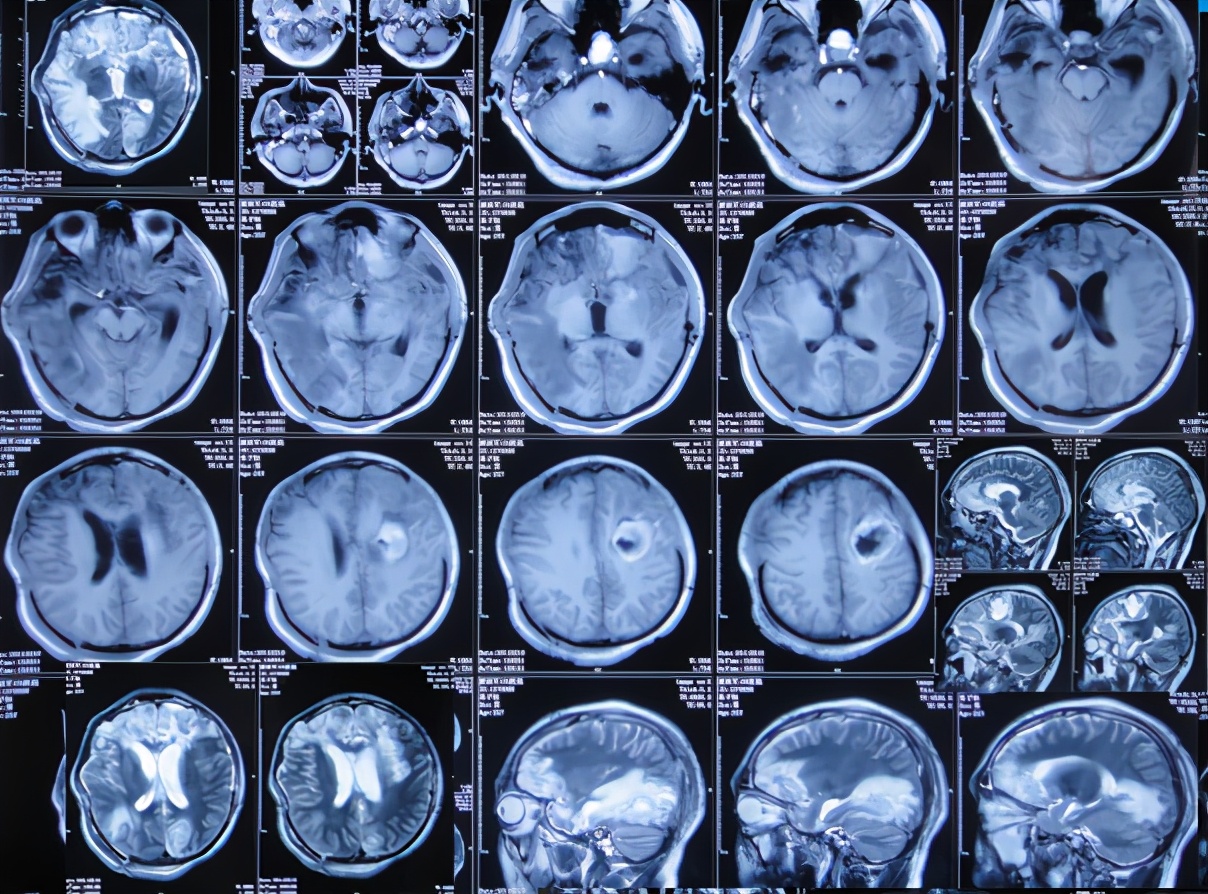

患者于2011年1月14日晚11点,意外发生车祸当即昏迷,120救护车将其送往第1家的安徽省合肥市的某三甲医院,查头颅CT:重度颅脑损伤,脑出血( 图-1 )。

图-1: 2011年1月15日头颅CT

当天急诊去骨瓣减压术;术后当天查头颅CT示双侧去骨瓣减压术后状态( 图-2 )。

图-2: 2011年1月15日术后头颅CT

术后患者生命渐趋稳定;但开颅术后26天即2011年2月10日,复查头颅MRI:轻度脑膨出,脑水肿( 图-3 )。

图-3: 2011年2月10日头颅MRI